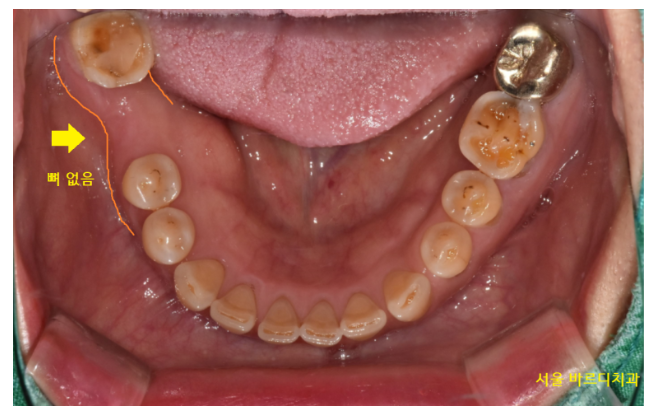

230713

아래 치아는 뼈가 부족한 부위가 있어도

이걸 보철로 하기에는 너무 아깝더라고요.

강동구 임플란트 할 공간도 충분하고...

보철 치료는 양 옆 멀쩡한 치아를 깎아야 해서요.